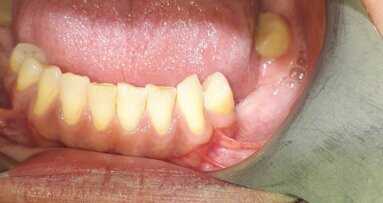

U pacjentki przeprowadzono zabiegi higienizacyjne (profesjonalne usuwanie złogów nazębnych nad- i poddziąsłowych). Wykonano konsultację pod kątem oceny funkcjonalnej (analiza zgryzu i fonetyki pacjenta). Stwierdzono cechy świadczące o nadmiernym starciu zębów związane z wykonywaniem parafunkcji (obgryzanie paznokci oraz skórek, nagryzanie wargi oraz nocne zaciskanie zębów).

Zdecydowano o wykonaniu zabiegu wstępnego zbalansowania warunków okluzyjnych oraz odbudowania startych kłów dolnych przy pomocy materiału kompozytowego. Następnie przystąpiono do wymiany zniszczonych wypełnień kompozytowych w zębach bocznych celem usunięcia próchnicy oraz zwiększenia liczby kontaktów w maksymalnym zaguzkowaniu zębów.

Wykonano wstępne zdjęcia zębów 18 i 17 po uprzednim sprawdzeniu istniejących kontaktów przy użyciu kalki progresywnej 200µ (Bausch Articulating Papers, Inc., Nashua, United States of America) oraz folii 8µ (Bausch Articulating Papers, Inc., Nashua, United States of America) (Ryc. 1). Następnie usunięto stare wypełnienia kompozytowe, próchnicę oraz zdemineralizowane tkanki zęba. Ubytki sprawdzono za pomocą preparatu Sable™ Seek® and Seek® Caries Indicator (Ultradent Products Inc., South Jordan, Utah, USA). Po założeniu koferdamu (Dental Dam Nic Tone, MDC Dental, Zapopan, Jalisco, Mexico) wykonano zdjęcie (Ryc. 2). Następnie zęby wytrawiono 38% kwasem ortofosforowym (Ultradent Products Inc., South Jordan, Utah, USA), spłukano za pomocą sprayu wodnego, osuszono, a następnie nałożono 2 warstwy systemu wiążącego (EnaBond, Micerium, Avegno, Włochy), przedmuchano oraz naświetlono lampą polimeryzacyjną (Elipar ™ S10 LED Curing Light, 3M ESPE, Neuss, Germany) przez 20 s.

Przystąpiono do warstwowej odbudowy zęba 17 za pomocą materiału kompozytowego zębinowego i szkliwnego (Enamel Plus HRi, Micerium, Avegno, Italy). Ząb 18 odbudowano za pomocą materiału kompozytowego płynnego (N – Fill Flow, MEGADENTA Dentalprodukte GmbH, Radeberg, Germany). W przypadku obu rekonstrukcji, do podbarwienia bruzd użyto farbki kompozytowej Stain ciemnobrązowej (Enamel Plus HFO, Micerium, Avegno, Italy) (Ryc. 3).

Po końcowym spolimeryzowaniu i zdjęciu koferdamu przystąpiono do korekty wypełnień w zgryzie przy użyciu kalki supercienkiej 40µ niebieskiej (Bausch Articulating Papers, Inc., Nashua, United States of America) (Ryc. 4), a następnie polerowano wypełnienia. Użyto do tego celu zestawu Shiny Finishing Kit (Enamel Plus, Micerium, Avegno, Italy ). Końcowy połysk odbudowy otrzymano za pomocą past polerskich z zestawu Polishing Paste Shiny Kit (Enamel Plus, Micerium, Avegno, Italy). Końcowy efekt widoczny jest na rycinie 5, a rycina 6 przedstawia stan z wizyty kontrolnej po 6 miesiącach.